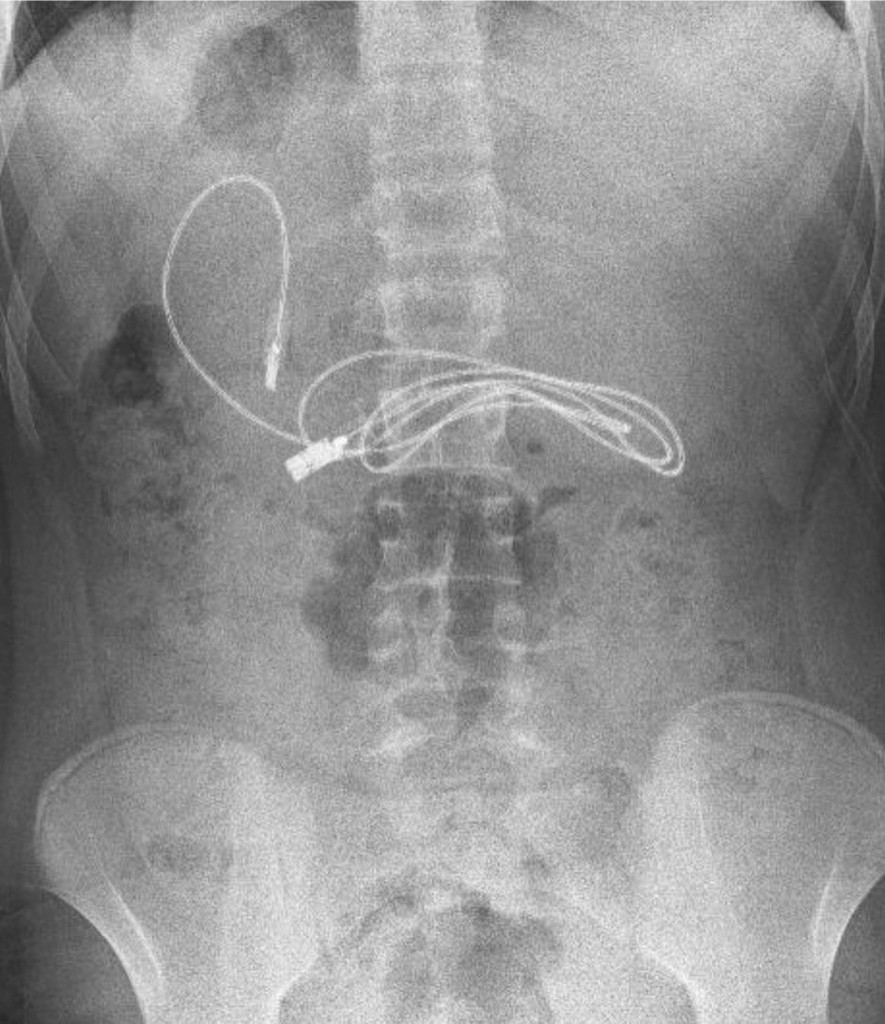

И причина болезненных симптомов оказалась странной. Когда 15-летнего подростка привезли на обследование в больницу, врачи обнаружили в его кишечнике USB-шнур для зарядки телефона длиной около метра.

Была проведена спешная эндоскопия, в результате которой доктора извлекли не только злосчастный шнур, но и резинку для волос.